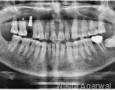

CBCT :

Yes

Pictures

Baseline